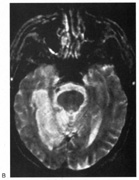

Fig. 18. Magnetic resonance imaging scan of patient with stroke causing a right hemiachromatopsia as well as partial superior quadrantanopia.